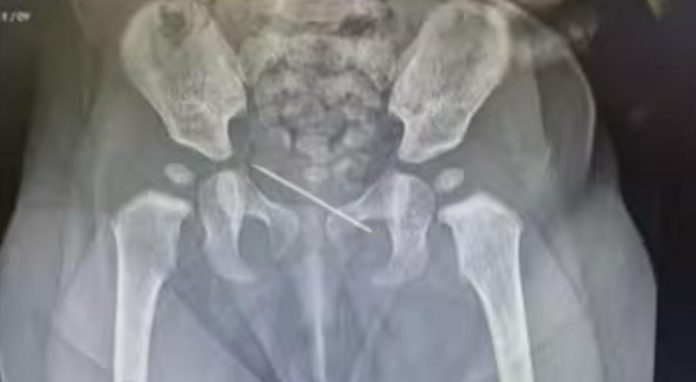

കുഞ്ഞിന്റെ സുരക്ഷ ഉറപ്പാക്കി കൊണ്ട് ലോക്കല് അനസ്തേഷ്യ നല്കി സിറിഞ്ച് സൂചി വിജയകരമായി പുറത്തെടുത്തു

നാഭിയില് ചര്മ്മത്തിന് താഴെ അസാധാരണ വസ്തു അനുഭവപ്പെട്ടതിനെ തുടര്ന്നാണ് ഏഴു മാസം പ്രായമുള്ള പെണ്കുഞ്ഞിനെ മുഹറഖിലെ അല് ഹിലാല് ആശുപത്രിയിലെത്തിച്ചത്. സ്പെഷ്യലിസ്റ്റ് പീഡിയാട്രീഷ്യന് ഡോ. ഗൗതം എം ശിവാനന്ദയെ കാണാനെത്തിയ കുട്ടിയെ പരിശോധനക്ക് വിധേയമാക്കിയപ്പോഴാണ് 3.5 സെന്റീമീറ്റര് നീളത്തിലുള്ള സിറിഞ്ച് സൂചി കണ്ടെത്തിയത്.

തുടര്ന്ന് കുഞ്ഞിന്റെ സുരക്ഷ ഉറപ്പാക്കി കൊണ്ട് ലോക്കല് അനസ്തേഷ്യ നല്കി സിറിഞ്ച് സൂചി വിജയകരമായി പുറത്തെടുത്തു. ശസ്ത്രക്രിയ വിജയകരമായതിനെ തുടര്ന്ന് കുഞ്ഞിനെ ആശുപത്രിയില് നിന്ന് ഡിസ്ചാര്ജ് ചെയ്തതായി ആശുപത്രി അധികൃതര് അറിയിച്ചു.